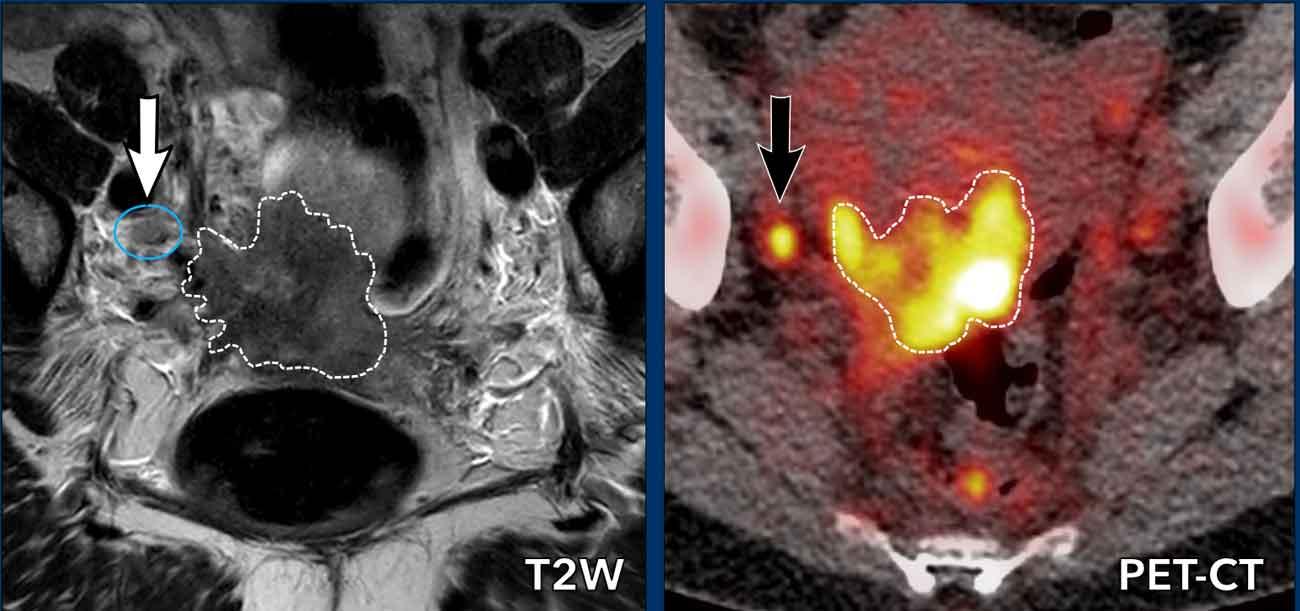

Hình ảnh

Có ung thư cổ tử cung tiến triển tại chỗ với xâm lấn cạnh cổ tử cung và thành bên chậu hông bên phải.

Có một hạch 7 mm ở mặt sau tĩnh mạch chậu ngoài phải (mũi tên trắng) không xác định được trên MRI.

Dựa vào kích thước, hạch này không rõ ràng là bệnh lý.

Trên PET/CT tương ứng, khối u nguyên phát bắt FDG rõ ràng, cũng như hạch cạnh chậu nhỏ (mũi tên đen), qua đó chẩn đoán là N+.